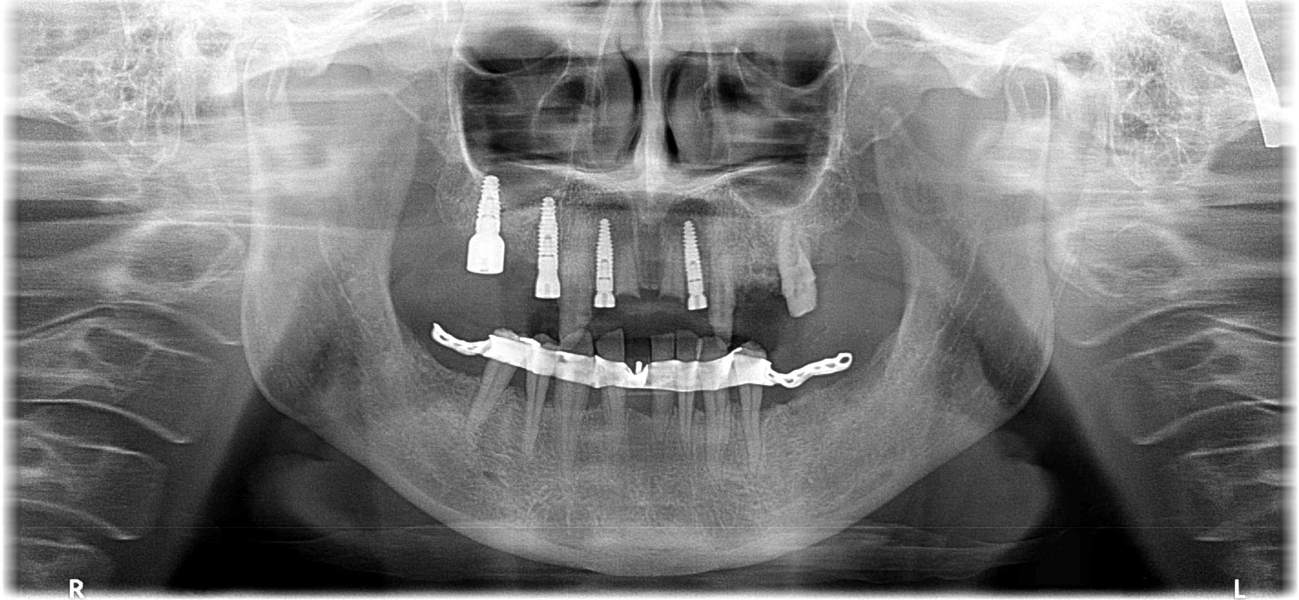

The 58-year-old, non-smoking and systemically healthy female patient was referred by her dentist to our dental clinic for implant treatment. The patient’s main complaints were poor aesthetics in the upper jaw, including a high smile line and distinct tooth pattern anomalies in the anterior maxilla (Figs. 1 & 2), as well as masticatory discomfort. Teeth #17, 15 and 27 were missing and had not undergone any prosthetic treatment, whereas the five missing teeth in the premolar and molar areas on both sides of the mandible had been replaced with a removable partial denture. All remaining teeth were affected by Stage IV periodontitis according to the 2017 Classification of Periodontal and Peri‐implant Diseases and Conditions, displaying a mean periodontal pocket depth of 5.6 mm.7 Mean bleeding on probing and mean plaque index were 70% and 80%, respectively. With respect to periodontal parameters, as well as to oral hygiene measures (visible calculus and dental plaque), the patient’s oral hygiene was graded as poor. The patient had been treated elsewhere with two implants in the posterior maxilla in order to replace the right first premolar and first molar (Fig. 3). She had a thick flat biotype, according to a definition introduced in 1977.8, 9

After obtaining informed consent from the patient, we would start dental rehabilitation in the maxilla, and we opted for a two-stage surgical approach after initial therapy. Initial therapy would consist of systematic periodontal treatment and regular recalls with instructions and checks for dental hygiene over a period of three months. The first stage of rehabilitation of the maxilla would consist of partial extraction therapy in conjunction with Type 1 implant placement in the regions of the teeth #12 and 22 according to the Proceedings of the Fourth ITI Consensus Conference and ridge preservation in the region of teeth #24 and 25 with particulate dentine, obtained and processed from the two extracted left maxillary premolar teeth.10 Owing to increased tooth mobility and the obvious poor buccal bone volume, as displayed on the CBCT scan (CRANEX 3D Ceph, Soredex, KaVo Kerr), regions #11 and 21 were not suitable for the socket shield technique in conjunction with implant placement (Fig. 4). Both central incisors were to be treated with the submerged root technique instead, in order to prevent damage of the buccal socket wall and volume loss of the alveolar ridge after tooth extraction. With both roots in place, a physiological pontic site development for the definitive restoration would be enabled. Based on periodontal re-evaluation after the initial therapy, only the two maxillary canines were considered worth preserving. The left first molar was to be temporarily retained in order to serve, in conjunction with the two canines, as an additional abutment tooth for fixation of the temporary bridge during the healing period. Crown preparation of the three remaining teeth would be done before surgical treatment, in order to prefabricate a temporary bridge for immediate fixed provisionalisation after the first surgery. The second surgical stage would consist ofimplant placement in region #24, performing of the socket shield technique on the mesiobuccal root, submersion of the distobuccal root and extraction of the palatal root of tooth #26 before immediate implant placement. Definitive prosthetic treatment would be performed after a transgingival implant healing period of at least three months, applying a conventional implant loading protocol with fixed bridges.11

Fig. 4: CBCT scan showing the bone condition of the maxillary teeth. Vertical resorption and reduced thickness of the buccal bone plate of the right and left central incisors were evident.